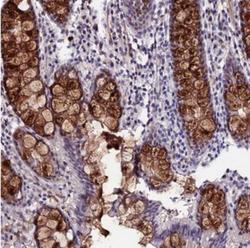

Supportive validation

- Submitted by

- Novus Biologicals (provider)

- Main image

- Experimental details

- Immunohistochemistry: SYT15 Antibody [NBP2-30856] - Staining of human colon shows strong cytoplasmic positivity in glandular cells.